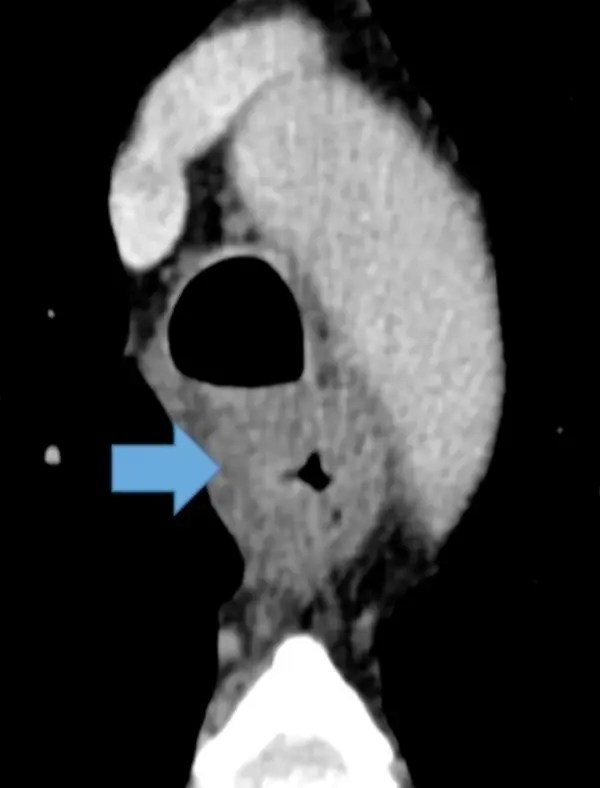

Example: 67 year old male with diffuse symmetric thickening of esophagus â Dx: Carcinoma